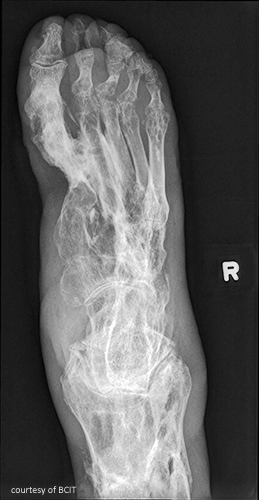

Common site for gout?

First MTP joint of the big toe.

Radiographic signs of gout?

Late changes: “mouse-bitten” erosions, overhanging edges, possible calcified tophi; no osteopenia.